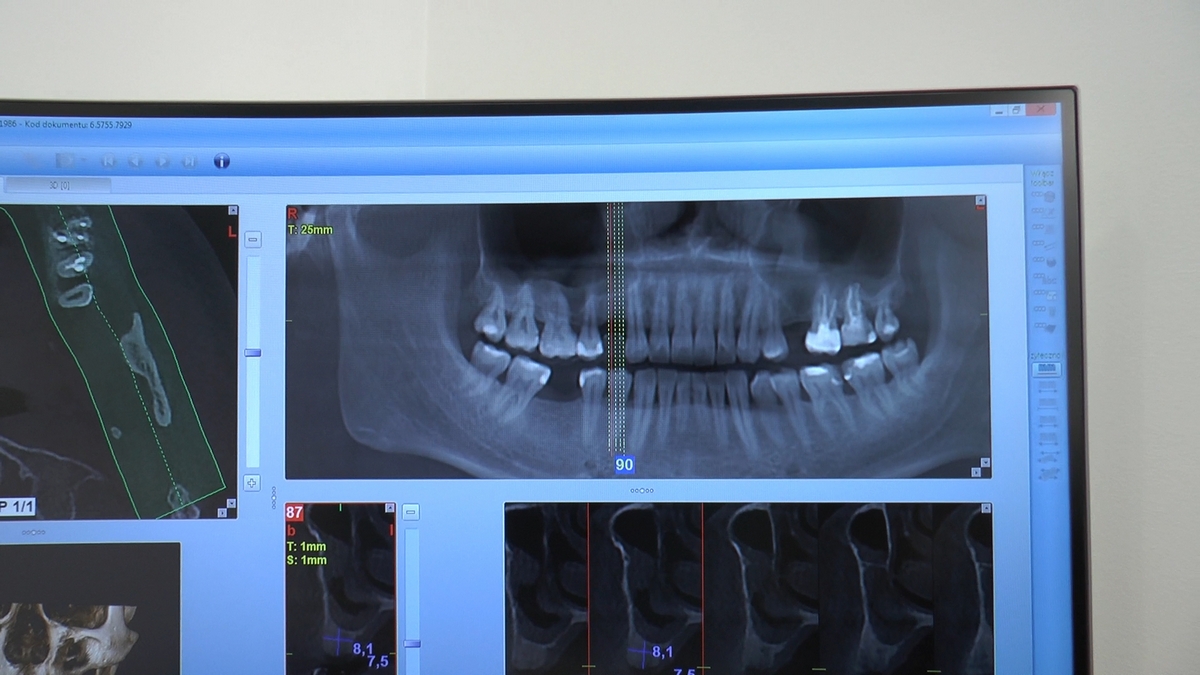

Wprowadziliśmy łącznie 25 implantów w tym wykonaliśmy:

dwa zabiegi All- on -4 / jeden w szczęce, jeden w żuchwie/ z usunięciem zębów i natychmiastową implantacją oraz natychmiastową odbudową protetyczną

jeden zabieg sinus lift otwarty